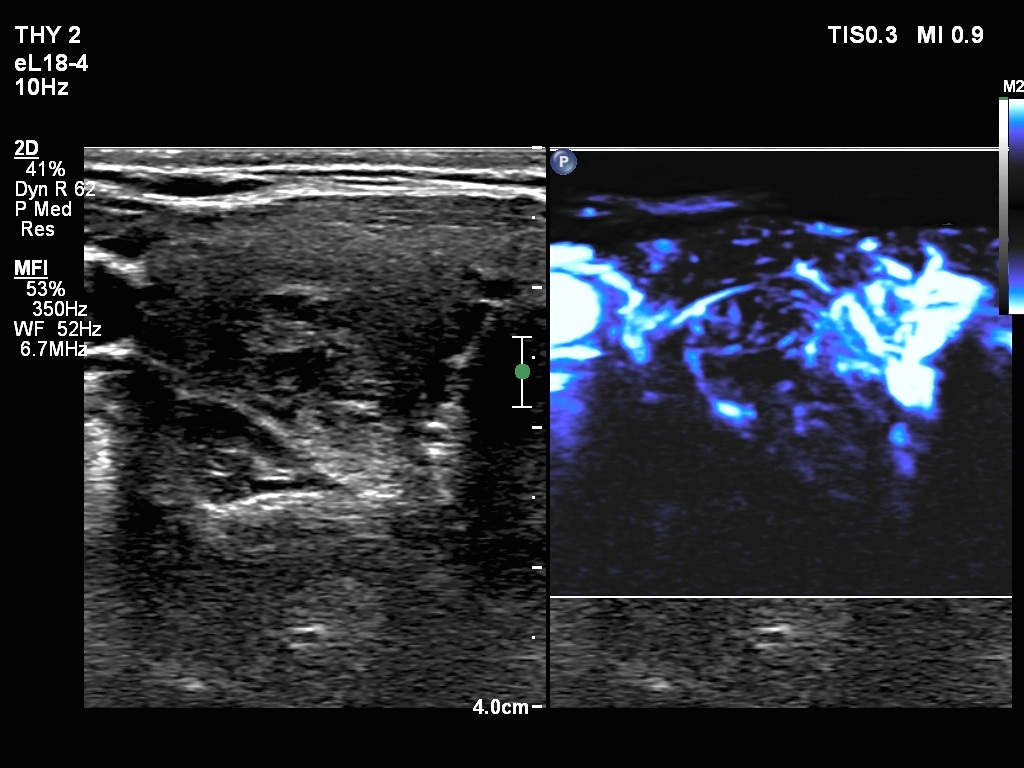

Ultrasonography. The thyroid was echonormal. There were two nodules in the right lobe. The upper was hyperechogenic-cystic while the lower was a minimally-moderately hypoechogenic. The latter had irregular, lobulated margins. There was a hypoechoic area in the upper two-third of left lobe. The discrete area presented ill-defined margins and decreased vascularization. A spongiform cyst was found in the lower pole of the left lobe.

Cytology of the nodule with irregular margins resulted in benign lesion, while cytology disclosed de Quervain's thyroiditis in the event of the hypoechoic area in the left lobe.